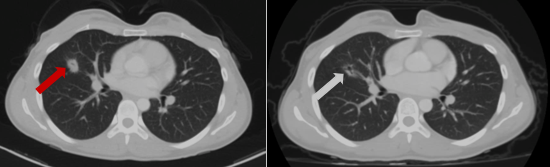

Sau đó bệnh nhân được chỉ định thêm các xét nghiệm cận lâm sàng khác. Trên phim chụp cắt lớp vi tính lồng ngực của bệnh nhân phát hiện khối u phổi dạng nang kích thước ~ 20x14mm ở thùy giữa phổi phải.

Hình 2. Hình ảnh khối u phổi phải trên phim chụp Cắt lớp vi tính ngày 27 tháng 10 năm 2022 (mũi tên).

Hình 3. Hình ảnh phim chụp cộng hưởng từ não ngày 28 tháng 6 năm 2023 (mũi tên trắng) so với ngày 27 tháng 10 năm 2022 (mũi tên đỏ), kích thước khối u giảm so với phim chụp cũ.

Hình 4. Hình ảnh phim chụp cắt lớp vi tính lồng ngực cho thấy kích thước khối u ngày 28 tháng 6 năm 2023 (mũi tên trắng) giảm hơn so với phim chụp ngày 27 tháng 10 năm 2022 (mũi tên đỏ).